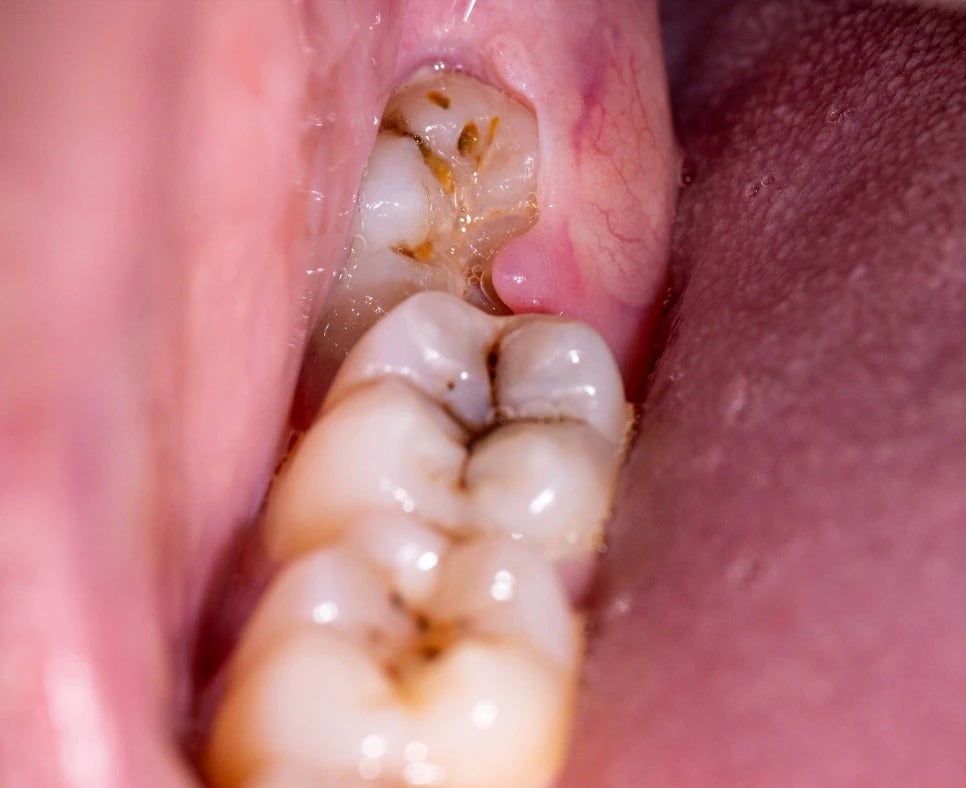

사진에서 보시다싶이 사랑니 주변에 빨갛게 염증이 생긴 경우를 자주 볼 수 있습니다. 환자분들께서 많이들 불편해하시죠 (출처: https://www.gumsurgery.com)

사랑니는

입 안 가장 안쪽에 위치해 있고,

완전히 나오지 않은 경우가 많습니다.

특히

사랑니가 부분적으로만 나온 상태에서는

잇몸과 치아 사이에

음식물과 세균이 쉽게 끼게 돼요 🤢